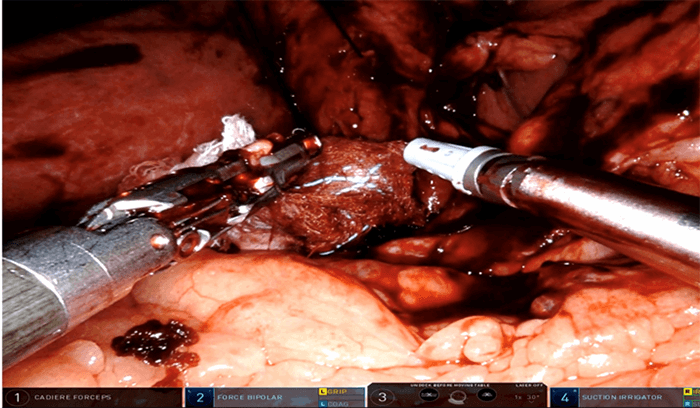

There were significant acute and subacute inflammatory adhesions around the gallbladder and cholecystostomy access site. The gallbladder had perforated into the liver. A single RF-tagged (4 x 4 in.) gauze was used during dissection to aid in hemostasis and visualization (Figure 1).

Figure 1. The intraoperative use of RF-tagged Ray-Tec gauze